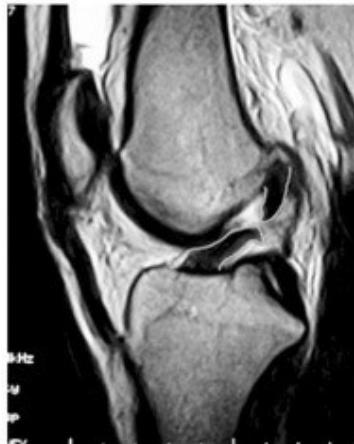

MRI (Gold Standard)

- Best imaging modality for ACL injuries

MRI Findings:

- Torn ACL